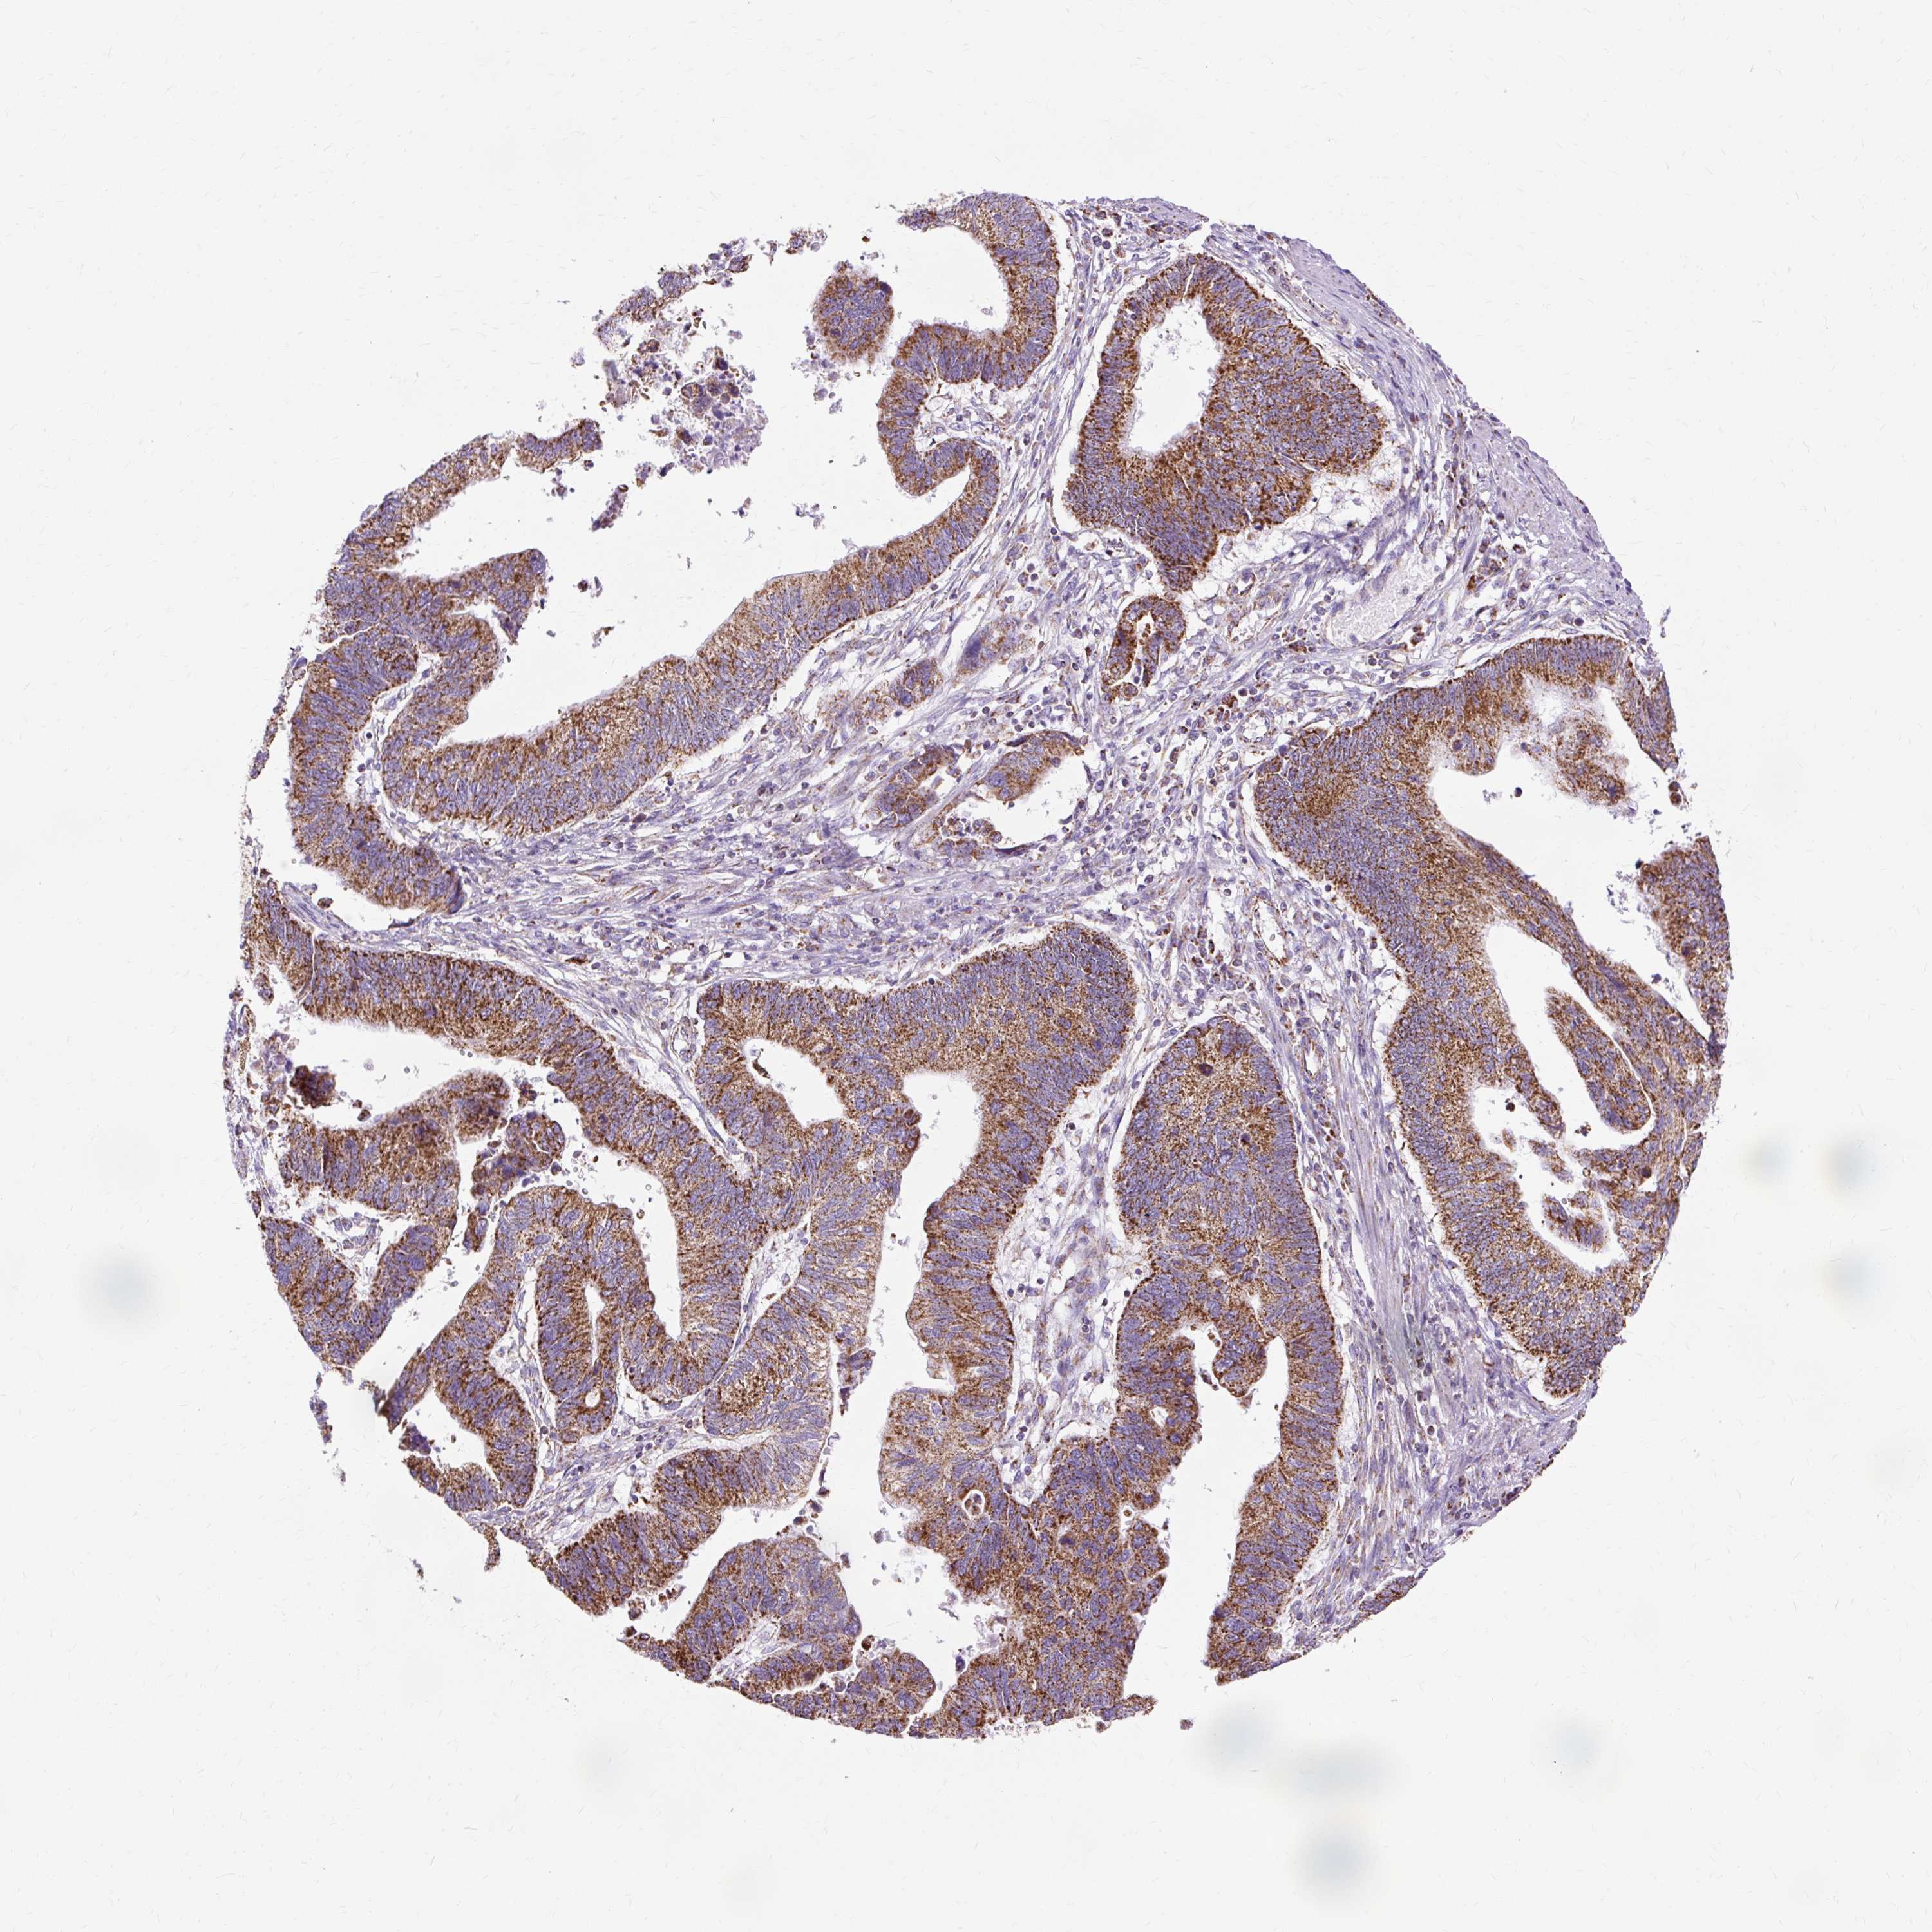

STOMACH CANCER - Protein expressioni

A mouse-over function shows sample information and annotation data. Click on an image to view it in a full screen mode. Samples can be filtered based on level of antibody staining by selecting one or several of the following categories: high, medium, low and not detected. The assay and annotation is described here.

Note that samples used for immunohistochemistry by the Human Protein Atlas do not correspond to samples in the TCGA dataset.

Antibody stainingi

Antibody staining in the annotated cell types in the current human tissue is reported as not detected, low, medium, or high, based on conventional immunohistochemistry profiling in selected tissues. This score is based on the combination of the staining intensity and fraction of stained cells.

Each image is clickable and will lead to virtual microscopy that enables deeper exploration of all samples and also displays staining intensity scores, fraction scores and subcellular localization as well as patient and tissue information for each sample.

Antibody HPA040786

Antibody CAB003782

Staining

High

Medium

Low

Not detected

Intensity

Strong

Moderate

Weak

Negative

Quantity

>75%

75%-25%

<25%

None

Location

Nuclear

Cytoplasmic/membranous

Cytoplasmic/membranous,nuclear

Adenocarcinoma, NOS